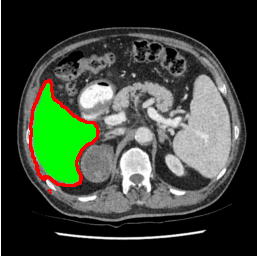

Our primary findings comparing the proposed model to baseline fully-supervised models when segmenting the liver from the LiTS dataset are reported in Table 1. The reported results demonstrate that our SAM-Mix model consistently achieves higher Dice scores compared to the fully supervised baselines as well as the two-stage SAM-PP method. Against U-Net, the best-performing fully supervised method, the SAM-Mix variant trained on 50 segmentation labeled slices (SAM-Mix-50), achieves a Dice score improvement of 5.9%. In terms of Hausdorff distance, while the fully-supervised baselines do slightly outperform SAM-Mix-5 and SAM-Mix-100, SAM-Mix-50 does achieve a lower Hausdorff distance by 22.38%. Qualitative evaluation as shown in Figs. 3 further affirms the superiority of SAM-Mix over baseline and existing fully-supervised methods as well as the two-stage SAM-PP variants. Furthermore, the boxplot visualization in Fig. 2 showcases consistently improved performance by SAM-Mix outperforming all the fully supervised and semi-supervised methods.